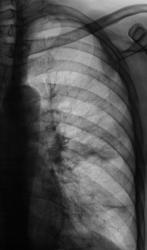

Флюорограмма.

Все просто до банальности. Пациент проходил профилактическое флюорографическое исследование органов грудной полости (жалоб нет), и сразу, в тот же день был взят мною на контроль по поводу подозрения на наличие "перибронхиального" рака и в течение 2-х часов "на нашем уровне дообследован", а на следующий день был срочно направлен в областной онкологический диспансер на консультацию "именно к специалистам" и на адекватное дообследование.

После проведенного рентгенологического исследования органов грудной полости - рентгенографии и томографии, при которой были выявлены увеличенные лимфатические узлы в корнях лёгких и средостении, было проведено рентгенотелевидение пищевода с прицельной рентгенографией и исследованием пищевода на трохоскопе, с контрастированием пищевода водной взвесью сернокислого бария "различной консистенции" - от сверхжидкого - до пастообразного, для "выяснения состояния" заднего средостения. Была зарегистрирована и документирована "локальная деформация пищевода" на протяжении 9,5 см. с перестройкой структуры "рельфа слизистой оболочки".